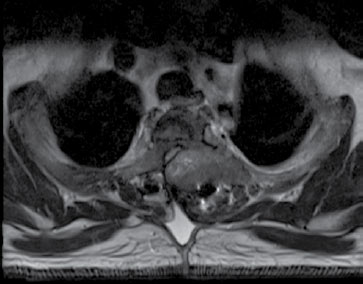

Dentro de los casos reportados, es usual que se realizaran múltiples estudios para enfocar la lesión entre los cuales se encuentran: radiografías en las que se observan lesiones líticas únicas o múltiples mal demarcadas en expansión, además de desmineralización generalizada. Por otro lado, la tomografía muestra mejor definición de la erosión local y extensión presentada no solo en hueso sino también en tejido blando, que se intensifica con el medio de contraste; sin embargo, no es específica para diagnosticar este tipo de tumores, porque no los distingue de otro tipo de lesiones. Por último, la Resonancia Magnética es de gran ayuda en la mejor caracterización de las lesiones y su extensión, éstas se ven usualmente hipointensas en la secuencia de T1, hiper o hipointensas en la secuencia de T2 (esto se lo debe al grado de su componente quístico), con realce posterior a la administración del medio de contraste por su alta vascularización, la formación de hemorragias intratumorales que generan niveles líquido-líquido. El compromiso en columna se caracteriza por ser de componente sólido, que frecuentemente causa destrucción de la corteza y extensión a tejidos blandos (figuras 1 al 4)(5).

| Figura 1. Corte transversal con secuencia T2: se observa lesión que compromete el cuerpo vertebral y los elementos posteriores principalmente del lado izquierdo, causando disminución severa del canal

central con compromiso del saco tecal, cordón medular y mielopatía compresiva